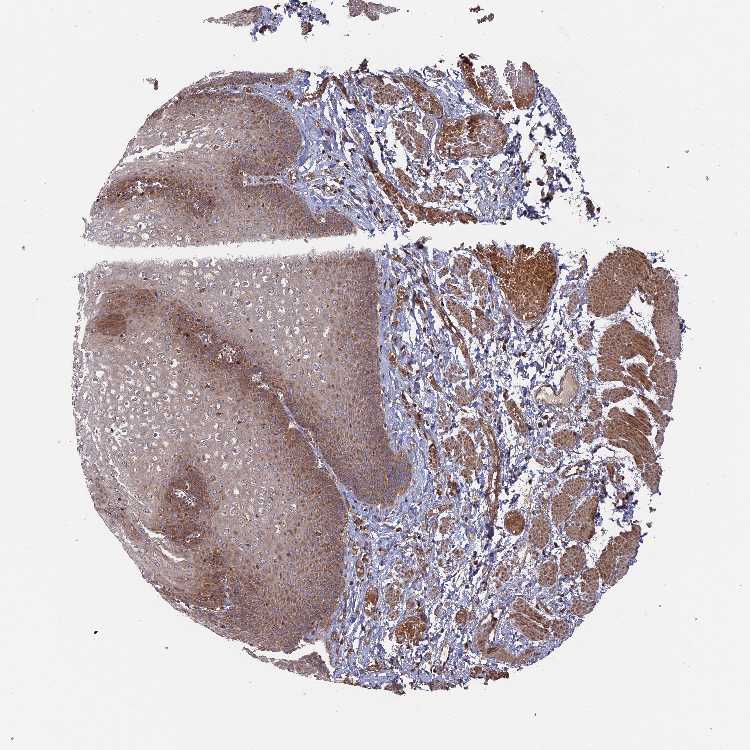

ESOPHAGUS - Antibody stainingi

Antibody staining in the annotated cell types in the current human tissue is reported as not detected, low, medium, or high, based on conventional immunohistochemistry profiling in selected tissues. This score is based on the combination of the staining intensity and fraction of stained cells.

Each image is clickable and will lead to virtual microscopy that enables deeper exploration of all samples and also displays staining intensity scores, fraction scores and subcellular localization as well as patient and tissue information for each sample.

Antibody HPA041348Antibody HPA041473

Squamous epithelial cells HighLow